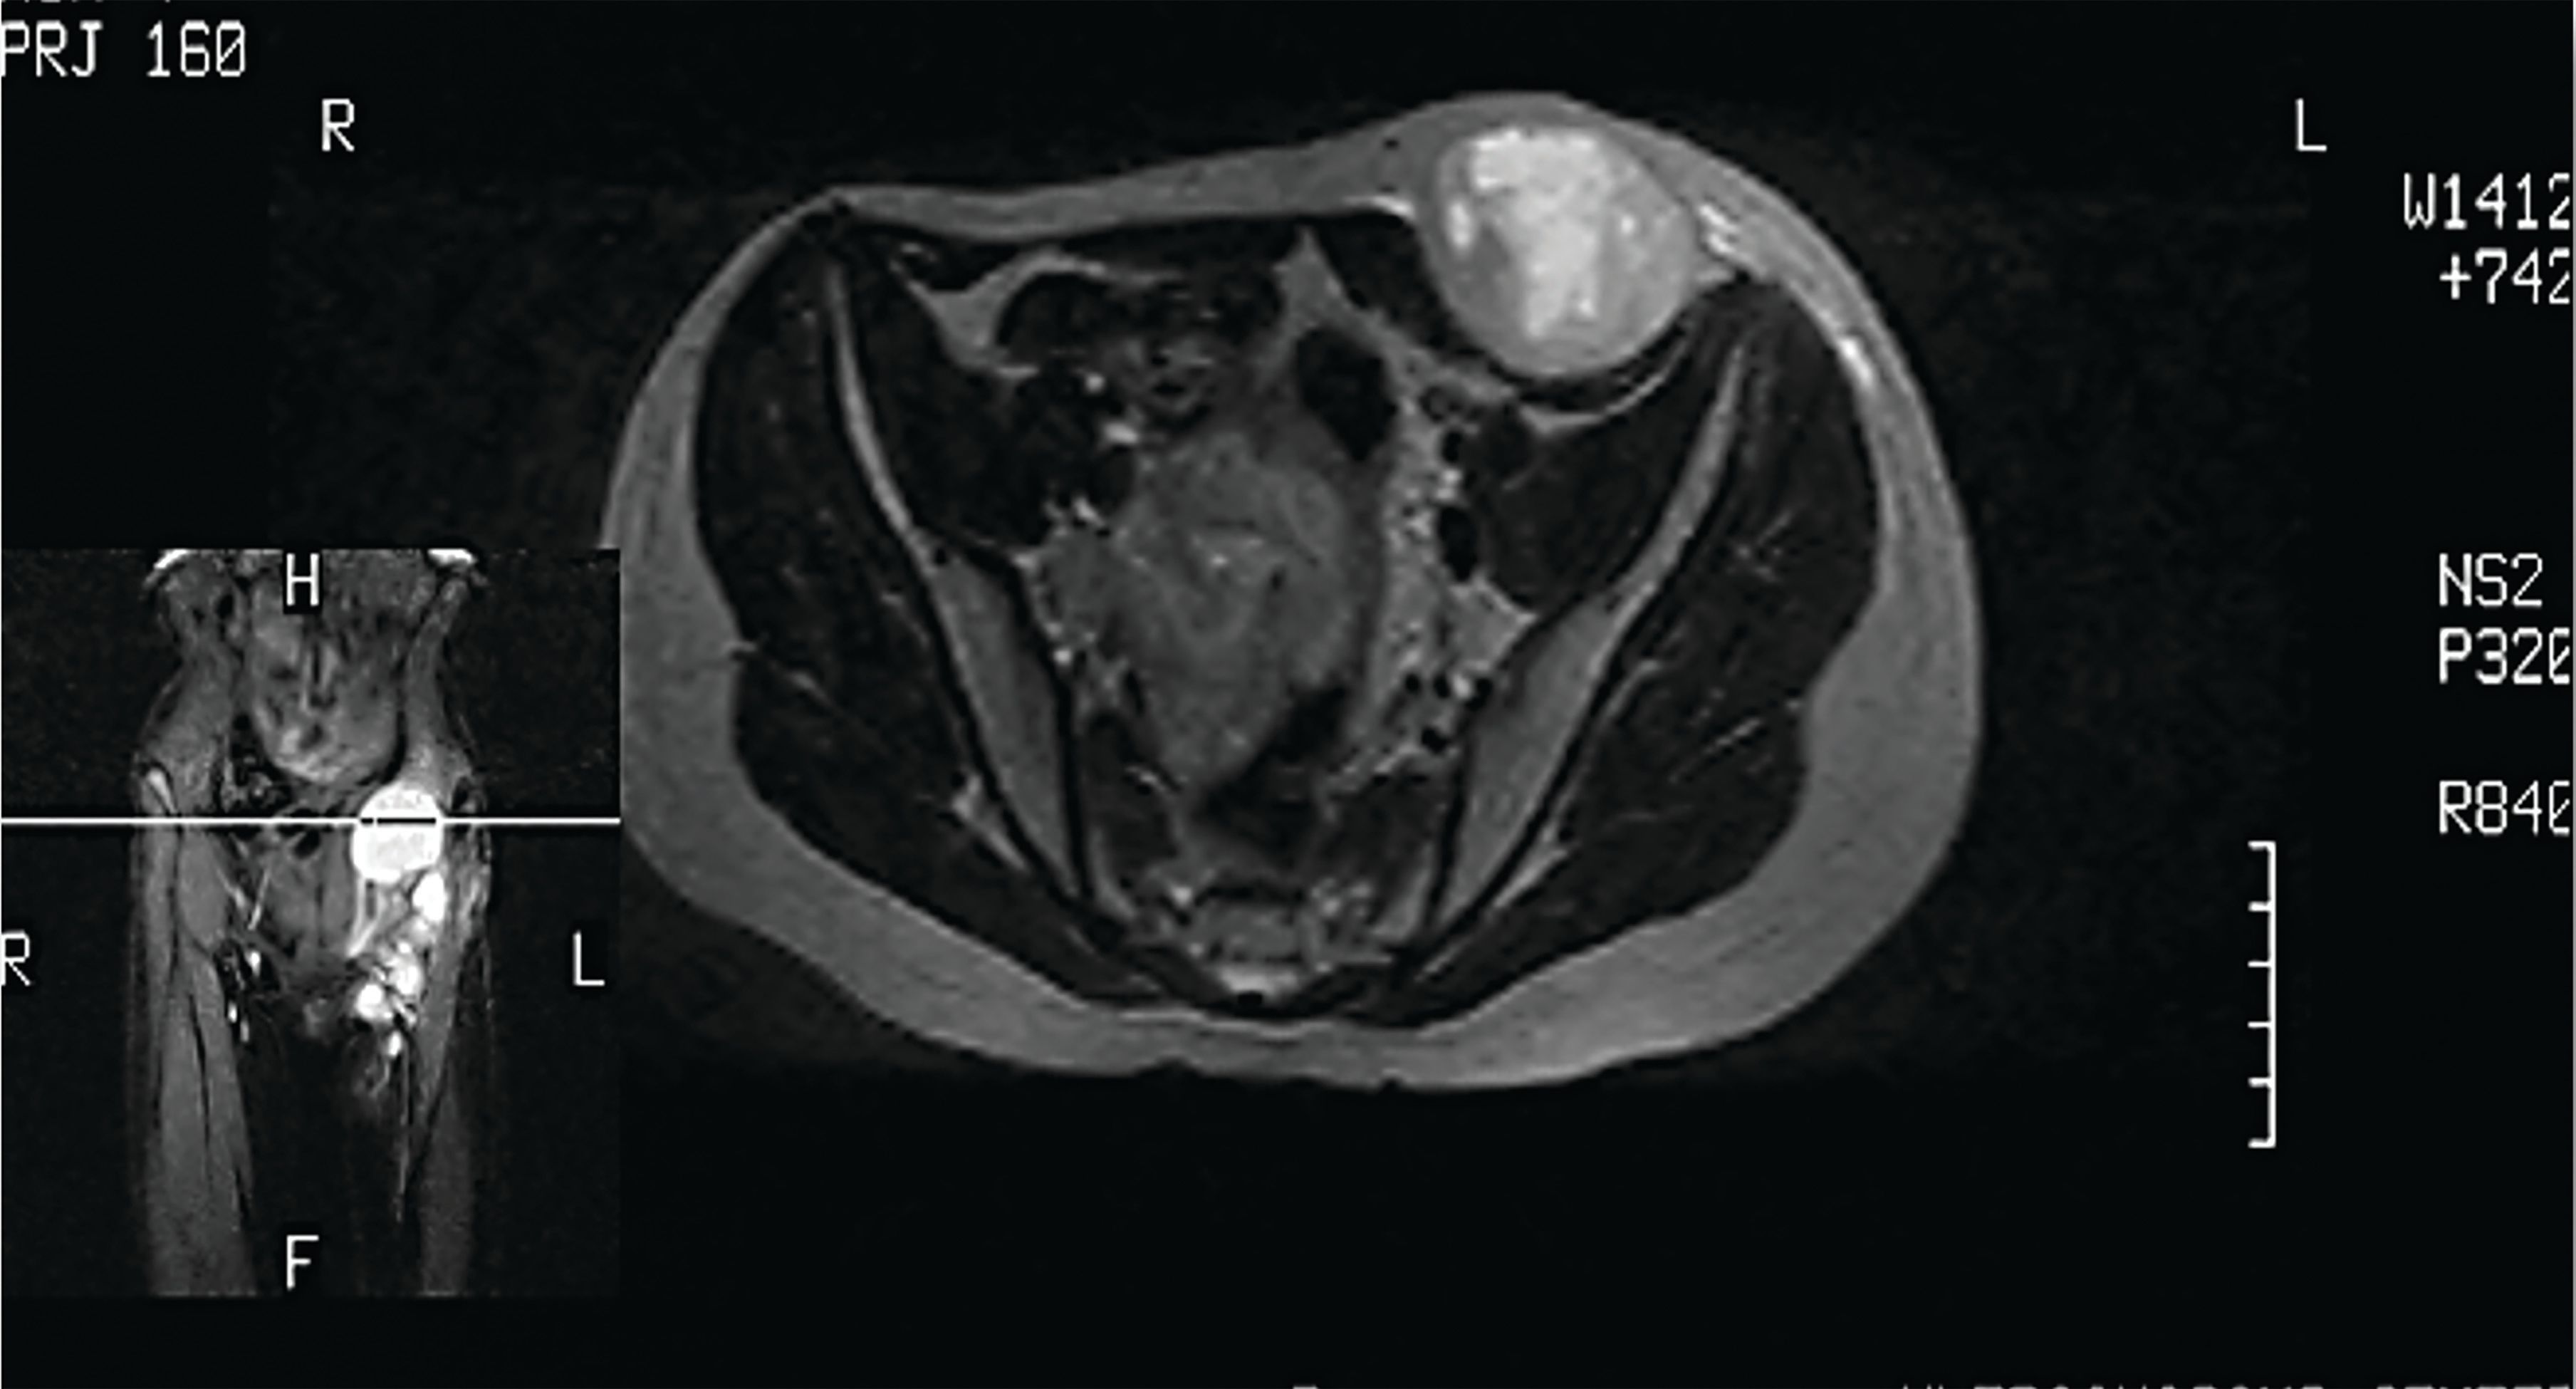

FIGURE 3a. The MRI Showed a Grape-Form Mass in the Abdominal Wall.

FIGURE 3b. The MRI Showed a Grape-Form Mass in the Abdominal Wall.

The patient’s parents initially refused further treatment. One year later, the patient noticed a painless mass beneath the postoperative scar on the anterior abdominal wall (Figure 2). The MRI revealed a grape-shaped, well-defined soft tissue mass in the left lower quadrant of the abdominal wall, measuring 15 cm (Figure 3). The CT showed left inguinal lymphadenopathy without signs of distant metastases. A bone scan revealed no abnormalities. A tumor biopsy confirmed disease relapse.